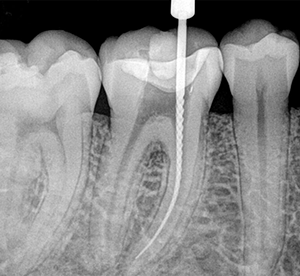

Root Canal Treatment (RCT)

A root canal is the space within the root of a tooth that is filled with pulp tissue (nerves and blood supply). Root canal treatments are valuable dental procedures used to treat and preserve teeth with infected roots. In a situation that a tooth is badly decayed or cracked that involves the pulp tissue, a removal of the pulp tissue (root canal treatment) is performed in order to save the tooth. To do sothe dentist drills into the pulp chamber and removes the pulp tissue. After this is done, the dentist fills each of the root canals with an inert material (gutta percha) and seals up the opening. After completion of the rooth canal in most cases the tooth is fitted with a crown to increase its longavity.